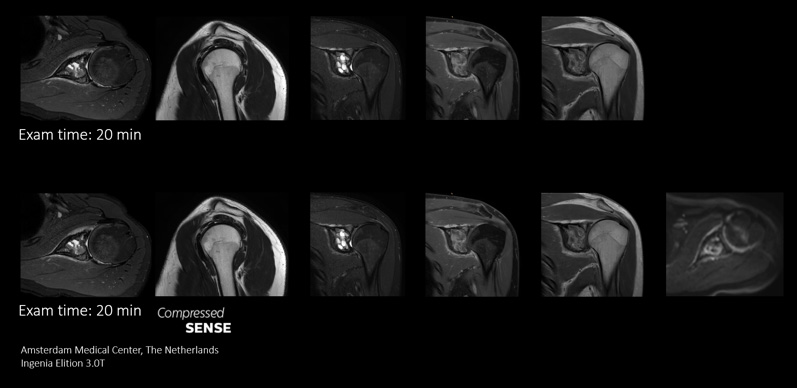

Zusätzliche Sequenzen

Mehr Informationen im gleichen Zeitfenster

Compressed SENSE gibt MR-Abteilungen die Flexibilität, innerhalb des Zeitfensters für einen MR-Scan so viele relevante Daten wie möglich zu erfassen. Die Geschwindigkeit von Compressed SENSE ermöglicht die Aufnahme von zusätzlichen routinemäßigen und funktionellen Sequenzen für zuverlässigere diagnostische Informationen.

Dieser Fall demonstriert die Möglichkeit, zusätzliche Sequenzen zum selben Zeitfenster hinzuzufügen und so letztendlich die Diagnosesicherheit zu erhöhen. Neben klassischen TSE-Sequenzen ist im selben Zeitfenster auch eine funktionelle Sequenz mit diffusionsgewichteter Bildgebung möglich, die zusätzliche Informationen für die Diagnosestellung liefert.

Die schnelleren Scans mit Compressed SENSE erlauben uns die Aufnahme einer zusätzlichen Sequenz. Wir erhalten so hochwertige Bilder für zuverlässige Diagnosen.“

Sachi Fukushima, MTRA, Kurashiki Zentralkrankenhaus, Japan